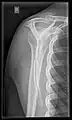

X-ray

Projectional radiography views of the shoulder include:

- AP-projection 40° posterior oblique after Grashey

The body has to be rotated about 30 to 45 degrees towards the shoulder to be imaged, and the standing or sitting patient lets the arm hang. This method reveals the joint gap and the vertical alignment towards the socket.[24]

- Transaxillary projection

The arm should be abducted 80 to 100 degrees. This method reveals:[24]

- The horizontal alignment of the humerus head in respect to the socket and the lateral clavicle in respect to the acromion

- Lesions of the anterior and posterior socket border, or of the tuberculum minus

- The eventual non-closure of the acromial apophysis

- The coraco-humeral interval

- Y-projection

The lateral contour of the shoulder should be positioned in front of the film in a way that the longitudinal axis of the scapula continues parallel to the path of the rays. This method reveals:[24]

- The horizontal centralization of the humerus head and socket

- The osseous margins of the coraco-acromial arch and hence the supraspinatus outlet canal

- The shape of the acromion

This projection has a low tolerance for errors and, accordingly, needs proper execution.[24] The Y-projection can be traced back to Wijnblath’s 1933 published cavitas-en-face projection.[25]

CR. shoulay film.

Transaxillary conventional radiography

Y-projection conventional radiography